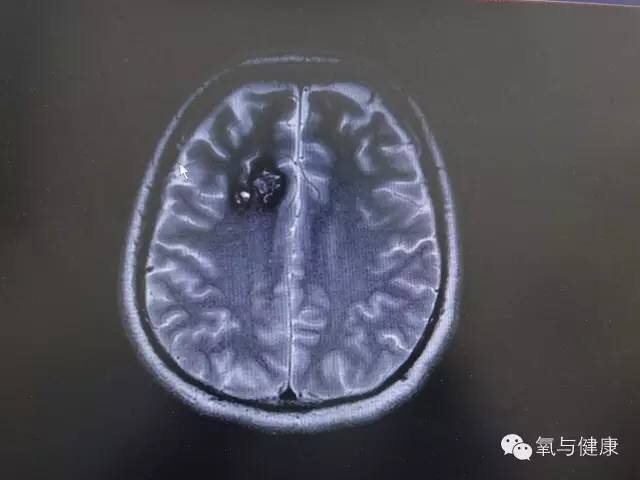

入院查体:神清、语利,高级智能查体正常。双瞳等,光反应灵,面纹对称,伸舌居中,四肢肌力、肌张力正常,病理征未引出。头磁共振(2015.08.25):右侧额叶异常信号,考虑海绵状血管瘤并少量出血。

图1:术前右侧额叶异常信号,考虑为海绵状血管瘤并少量出血